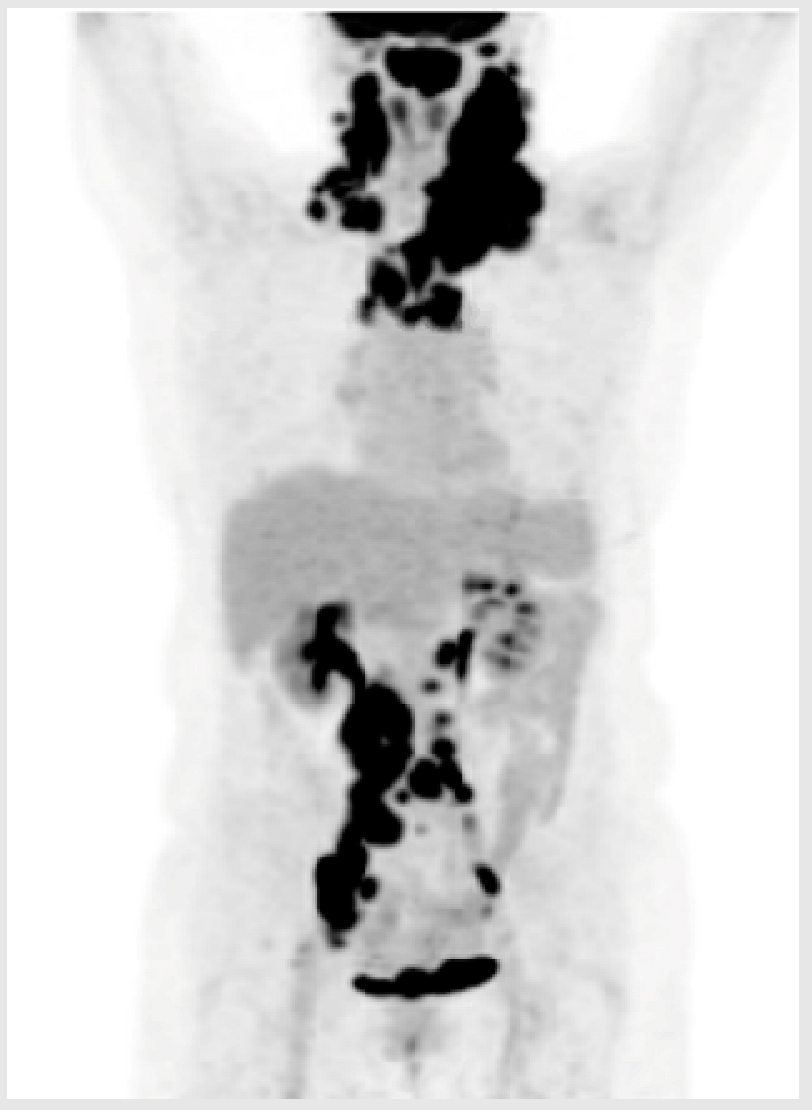

3.1. Illustrative Case 1

Key clinical features

| ![]() |

BsAb—bispecific antibody; BR—bendamustine–rituximab; CT—computerized tomography; CR—complete response; DLBCL—diffuse large B-cell lymphoma; ECOG—Eastern Cooperative Oncology Group; LDH—lactate dehydrogenase; PET—positron emission tomography; PS—performance status; ULN—upper limit of normal.

Key Points for Illustrative Case 1

- Guidelines for CAR-T cell therapy eligibility may vary somewhat between centers, but patients must meet a minimal level of fitness to be considered;

- Eligibility for CAR-T cell therapy is based on key clinical factors, including adequate cardiac function and a minimum renal function (CrCl greater than 30–45 mL/min). Age and traditional eligibility criteria for HDT-ASCT are less emphasized in favor of general performance status and comorbidities (target ECOG performance score: 0–2);

- Given the manufacturing time for CAR-T cells, a moderate tumor burden and moderate progression kinetics are necessary to ensure a safe waiting period and treatment trajectory. Rapid disease progression and high tumor burden can compromise general performance status and CAR-T cell efficacy, due to the unpredictable effectiveness of bridging therapies [28];

- Many patients will need to travel within their province or to another province to receive CAR-T cell therapy, which requires a suitable performance status. For individuals with comorbidities or symptoms due to lymphoma progression that limit their ability to travel, BsAbs may be a more practical and accessible treatment alternative;

- Additionally, the need for a caregiver can also be a limiting factor, either due to the caregiver’s unavailability or the patient’s feeling of being a burden;

- Given that BsAbs and CAR-T cell therapy currently target distinct antigens, CD20 and CD19, respectively, a referral for CAR-T cell therapy could be subsequently considered if the patient’s overall condition improves with BsAbs. However, considering this patient’s age of 75 years and her history of multiple comorbidities, the CAR-T cell process may not be feasible and BsAbs may be the preferrable alternative option.